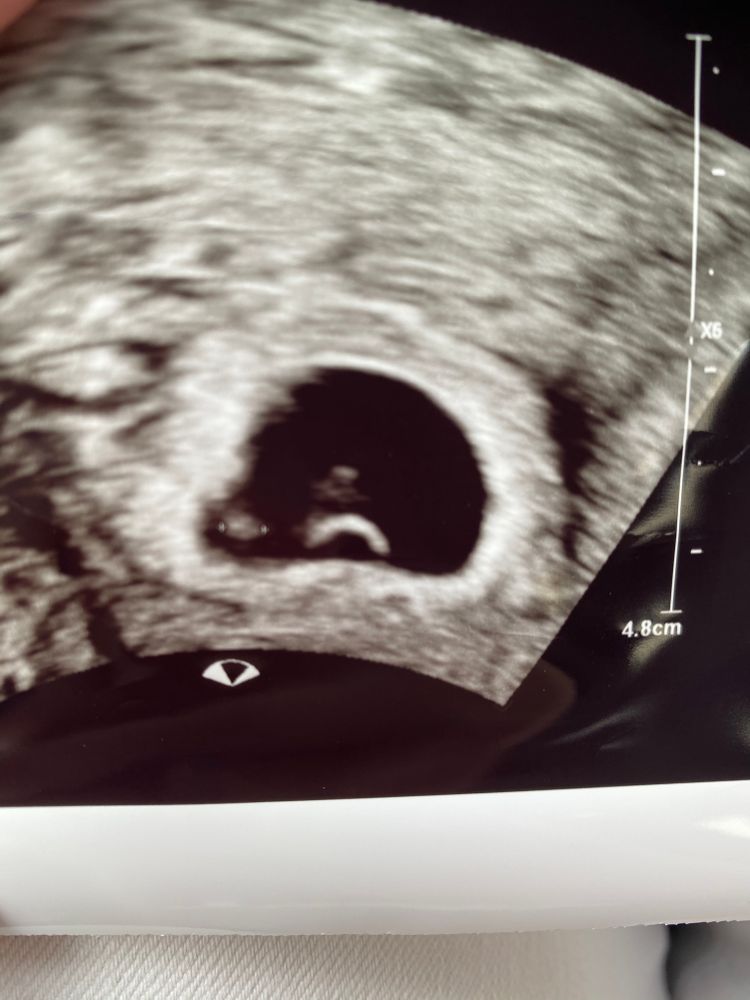

Беременность- 1 триместр ( только до 10 недель)Девочки,нас нашли,все хорошо)) Слева эмбрион 2 мм, внизу желточный мешочек,а что над ним?? Это случайно не два эмбриона?

Я что то и не спросила у врача, она быстро узи делала. Крови взяли 4 флакона, теперь через 4 недели за картой беременных. Срок день в день,5 недель 6 дней.

Чсс еще не слушали? Мне почему-то кажется, что эмбрион как раз сверху мешочка. А вот с лева не похоже на эмбрион. Хотя, вы так рано пошли, что там не разобрать. При двух эмбрионах однояйцевых должно быть тогда 2 жм